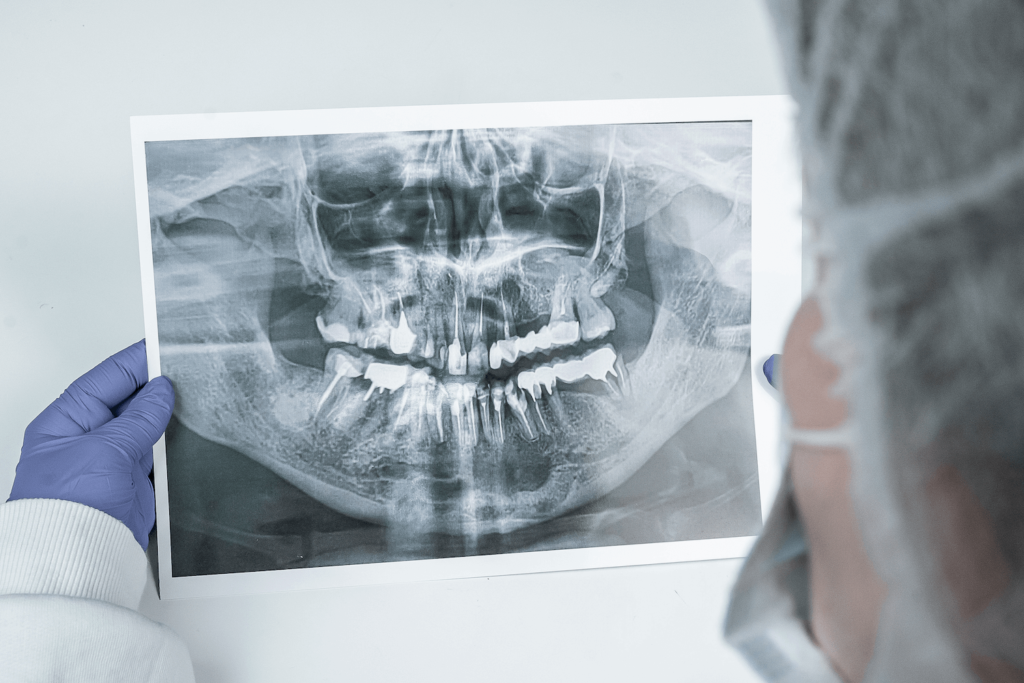

Около десяти лет назад к нашему врачу Максиму Макаренко обратилась пациентка с целью получить альтернативное мнение врача. Во время диагностики на панорамном снимке врач обнаружил интактные (здоровые) зубы на нижней челюсти и в области подбородка, в области апексов фронтальных зубов кисту с четким очертанием. Киста была достаточно большого размера, а именно от зуба 4.5 до зуба 3.5. То есть почти все зубы нижней челюсти были поражены новообразованием.

После осмотра, изучения ОПТГ-снимка и выслушав жалобы пациентки, врач обнаружил зуб, вызвавший образование кисты (зуб 3.2) и предложил лечение, которое позволит сохранить все зубы. Пациентка согласилась на лечение, состоявшее из следующих этапов: